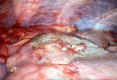

Osteochondromas are a very common and usually asymptomatic entity which may originate anywhere in the appendicular and axial skeleton. However, the ribs are a rare site of origin and here they may prove symptomatic for mechanical reasons. In this case report, we describe an unusual case of a symptomatic osteochondroma of the rib secondary to its location and unique shape, ultimately requiring surgical intervention.